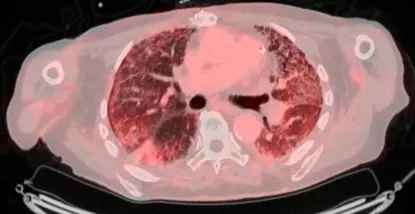

Pour aller plus loin dans la lutte contre cette maladie, le service de Pneumologie de l'Hôpital Erasme a initié une collaboration étroite avec le service de médecine nucléaire (Professeur P. Flamen et le Dr A. Deleu) pour développer un projet novateur d'imagerie moléculaire par PET/CT dans le but de visualiser l'activité de la maladie : le projet FAPI-PET.

​Le principe est d'utiliser un traceur radioactif qui va se lier aux cellules qui fabriquent la fibrose, les fibroblastes. Cette technologie révolutionnaire a déjà fait l'objet d'une première étude prometteuse sur 50 patients, financée grâce aux donateurs du Fonds Erasme. Les résultats, d'ores et déjà présentés lors d'un grand congrès européen de pneumologie et prévus pour une présentation actualisée à Barcelone, sont particulièrement excitants. L'équipe médicale a identifié un seuil (cut-off) du SUVmean : si l'activité mesurée au PET scan dépasse ce seuil, il est possible de prédire avec une sensibilité et une spécificité supérieures à 90 % que la maladie va progresser dans l'année avec un risque significativement plus élevé de décès.

Cette capacité à pronostiquer l'évolution de la fibrose permet d'entrer de plain-pied dans l'ère de la médecine personnalisée. En effet, actuellement, tous les patients reçoivent un traitement standard et on regarde comment la maladie évolue au cours du temps, ce qui fait perdre un temps précieux. Avec le FAPI-PET, le spécialiste peut adapter son approche : face à un patient dont le scan montre une faible activité, le médecin optera pour un suivi sans traitement immédiat ou à faible dose, évitant ainsi des effets secondaires inutiles.